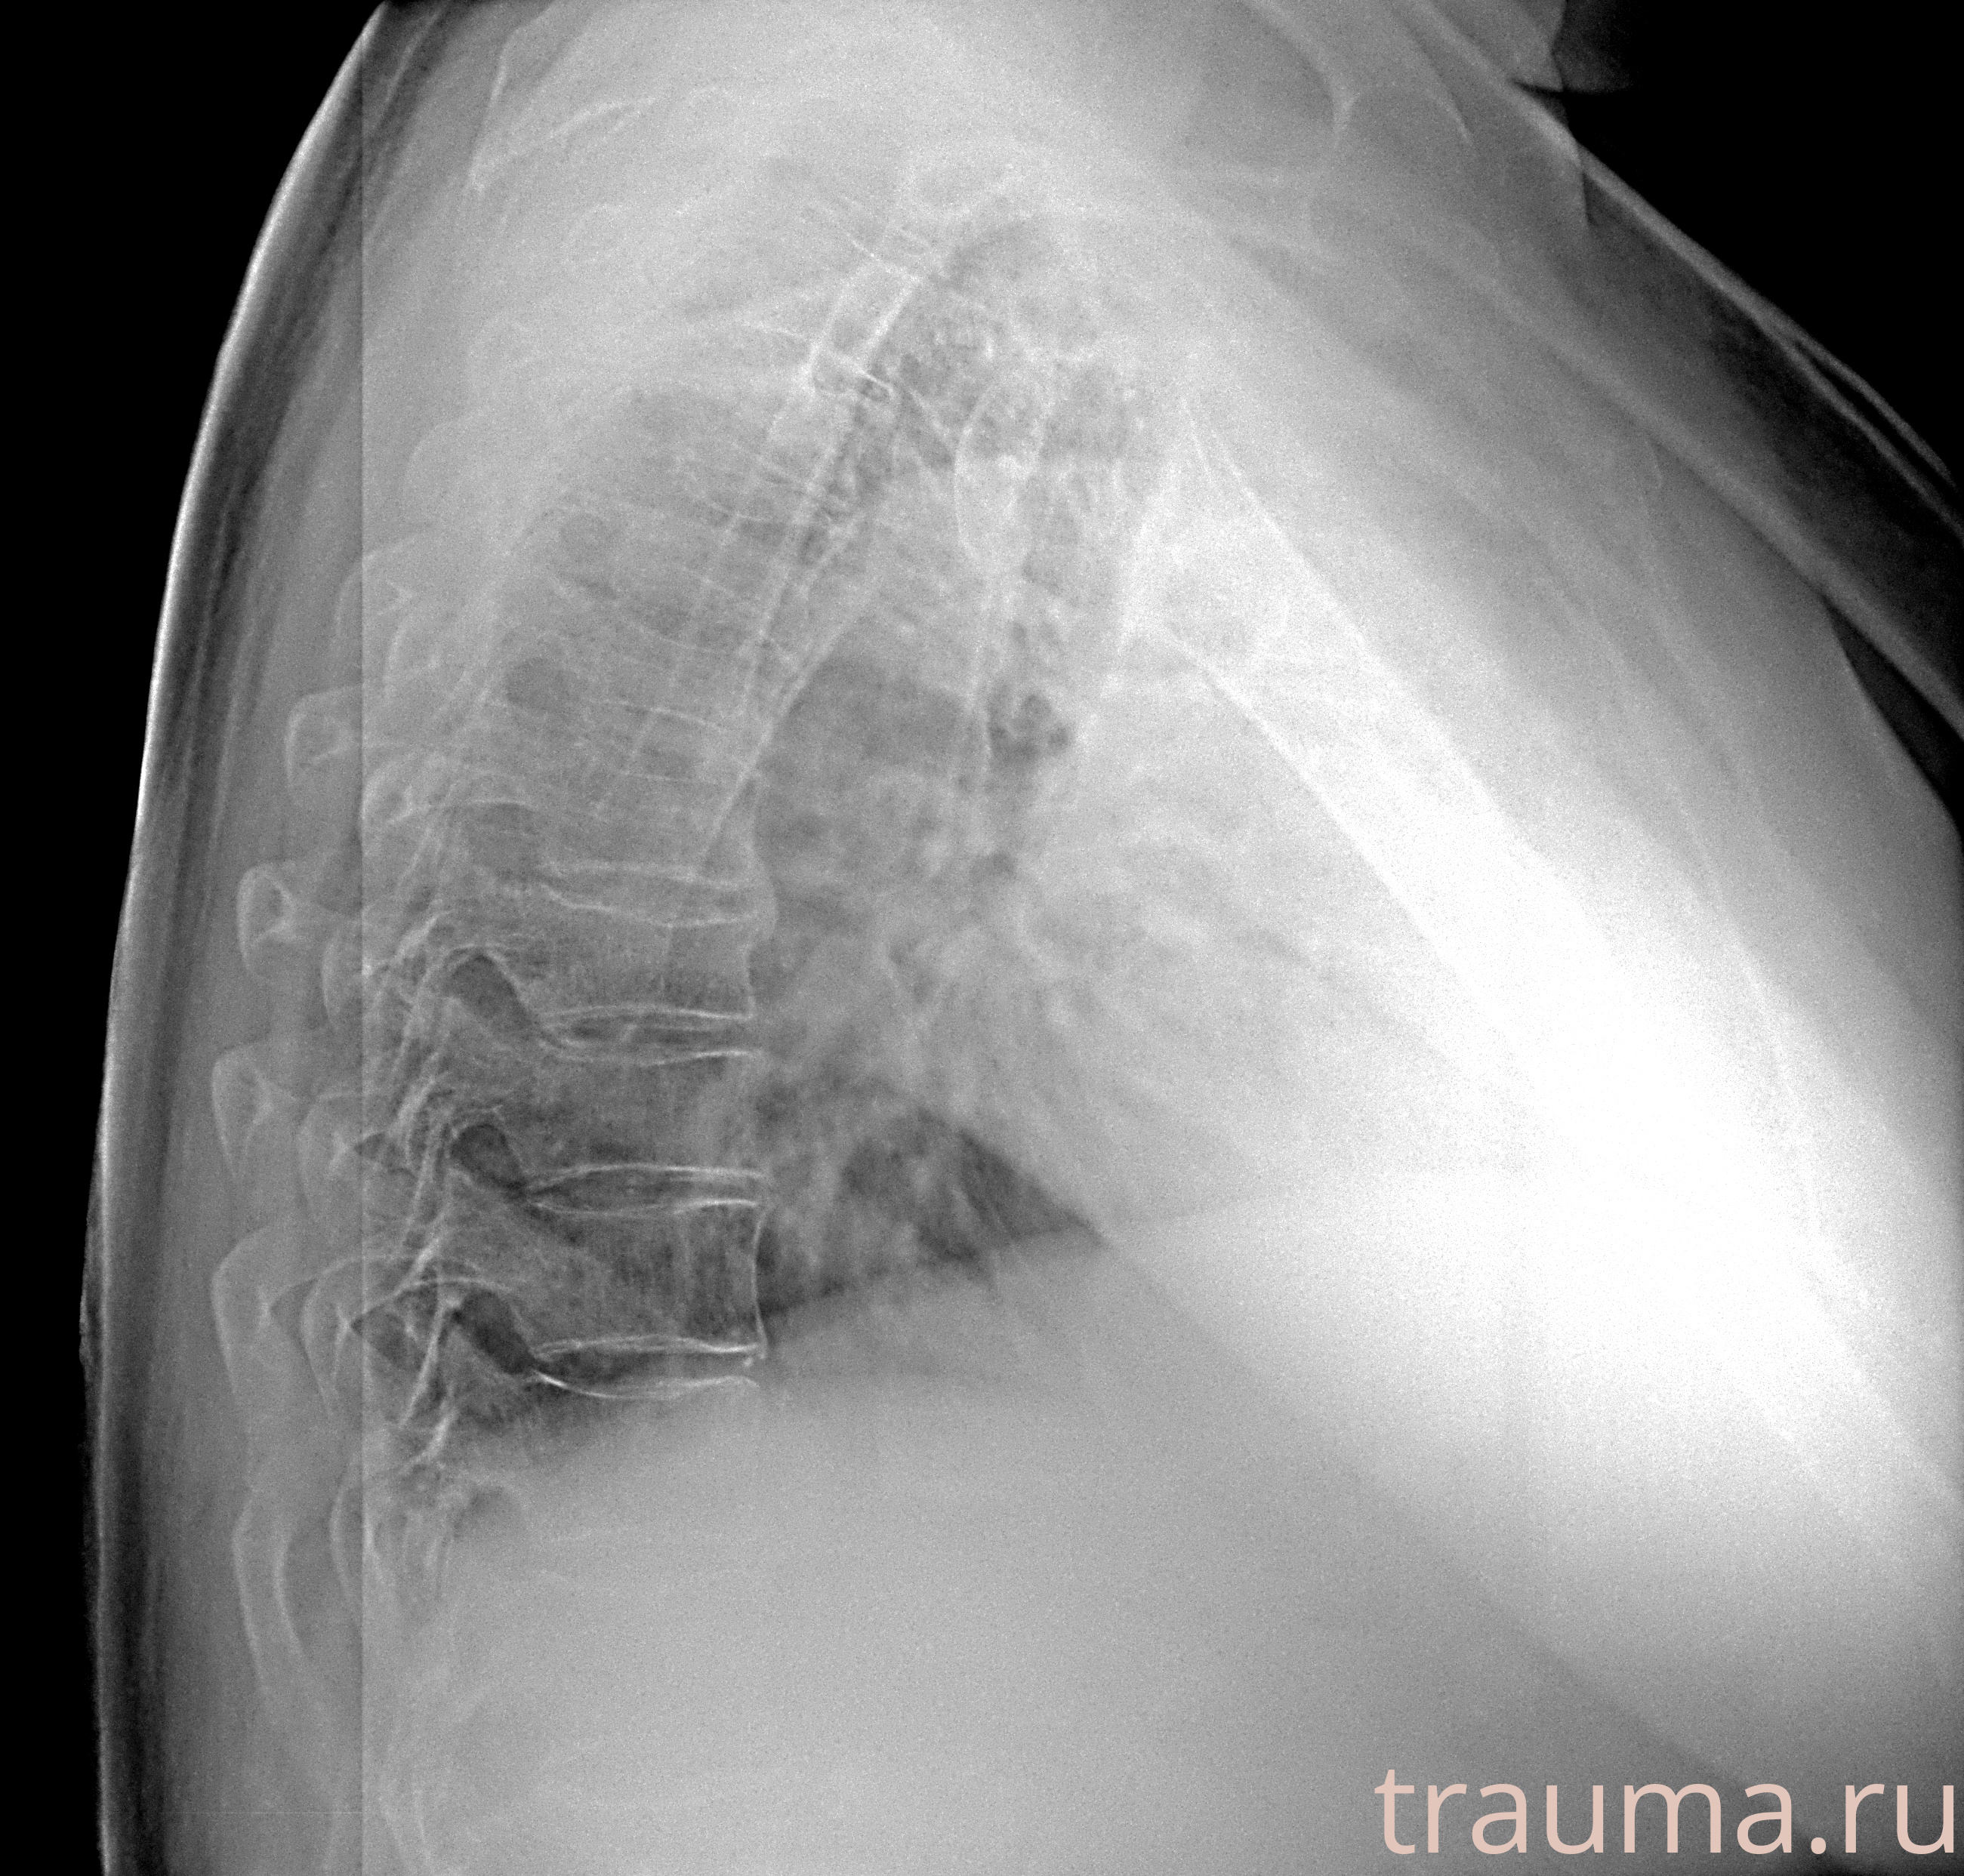

Рентгенограммы

Рентген на дому: по вашему адресу приезжает врач-рентгенолог, травматолог-ортопед с мобильным рентгеновским аппаратом, проводит диагностику травмы или заболевания, делает необходимые рентгенограммы, дает рекомендации по дальнейшему лечению. Получить качественные снимки в домашних условиях возможно благодаря уникальной методике, разработанной МосРентген Центром для института  Склифосовского

при переломе шейки бедра и пневмонии от компании МосРентген Центр - партнера Института имени Склифосовского